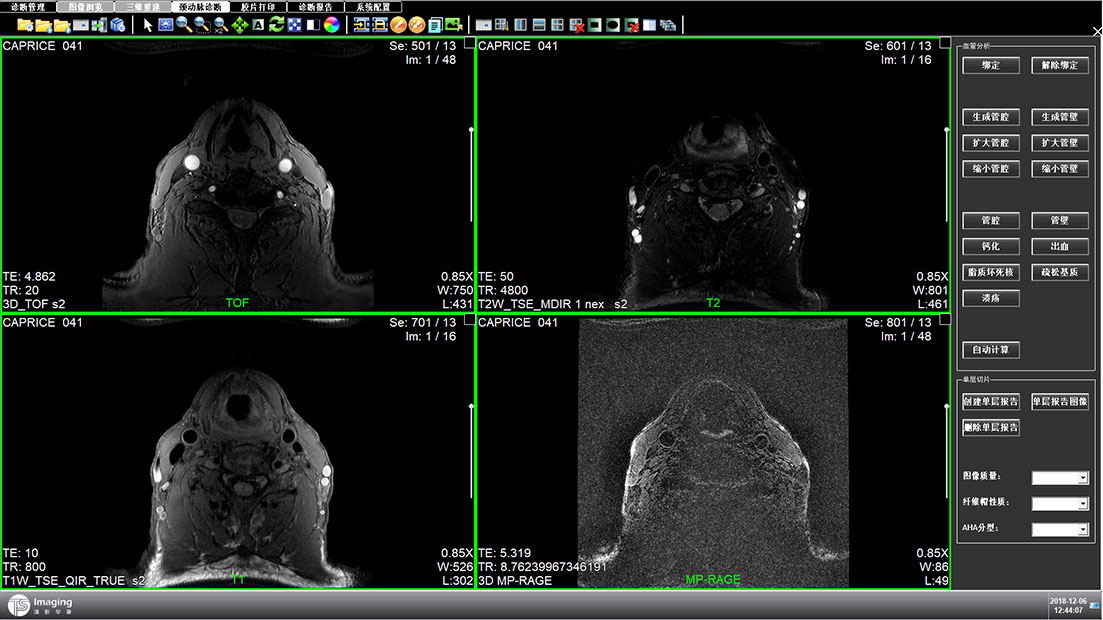

頸動(dòng)脈診斷頁面

頸動(dòng)脈診斷頁面整體布局和三維重建比較相似,最大的區(qū)別是右側(cè)的操作區(qū)域,血管分析都為按鍵操作,通過間隔的大小分成三部分。單層切片除了按鍵還有下拉菜單的操作。

頸動(dòng)脈診斷原型